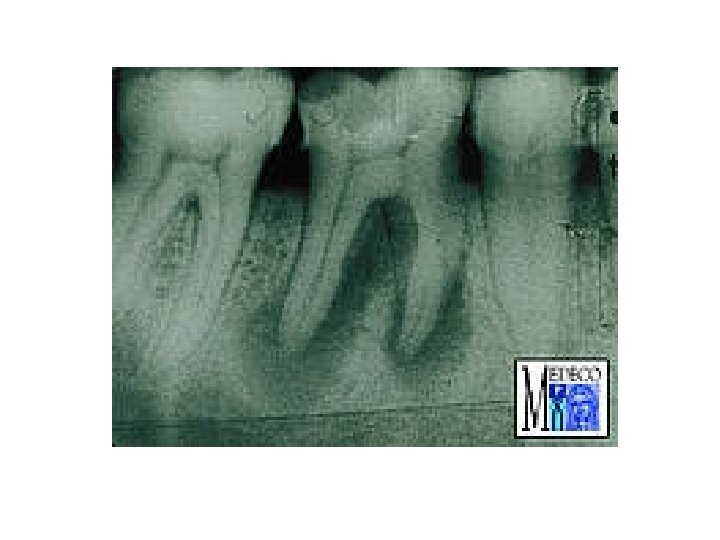

Granuloma periapicale • abgekapselte Ansammlung von Granulationsgewebe • Symptome: Keine Schmerzen, Devitalität des betroffenen Zahnes. • Röntgen: rundliche Form, scharfe Grenze, periapikale Aufhellung • Histologie: Cyst > 1 cm (Fluidum) Granuloma < 1 cm (Granulationsgewebe)